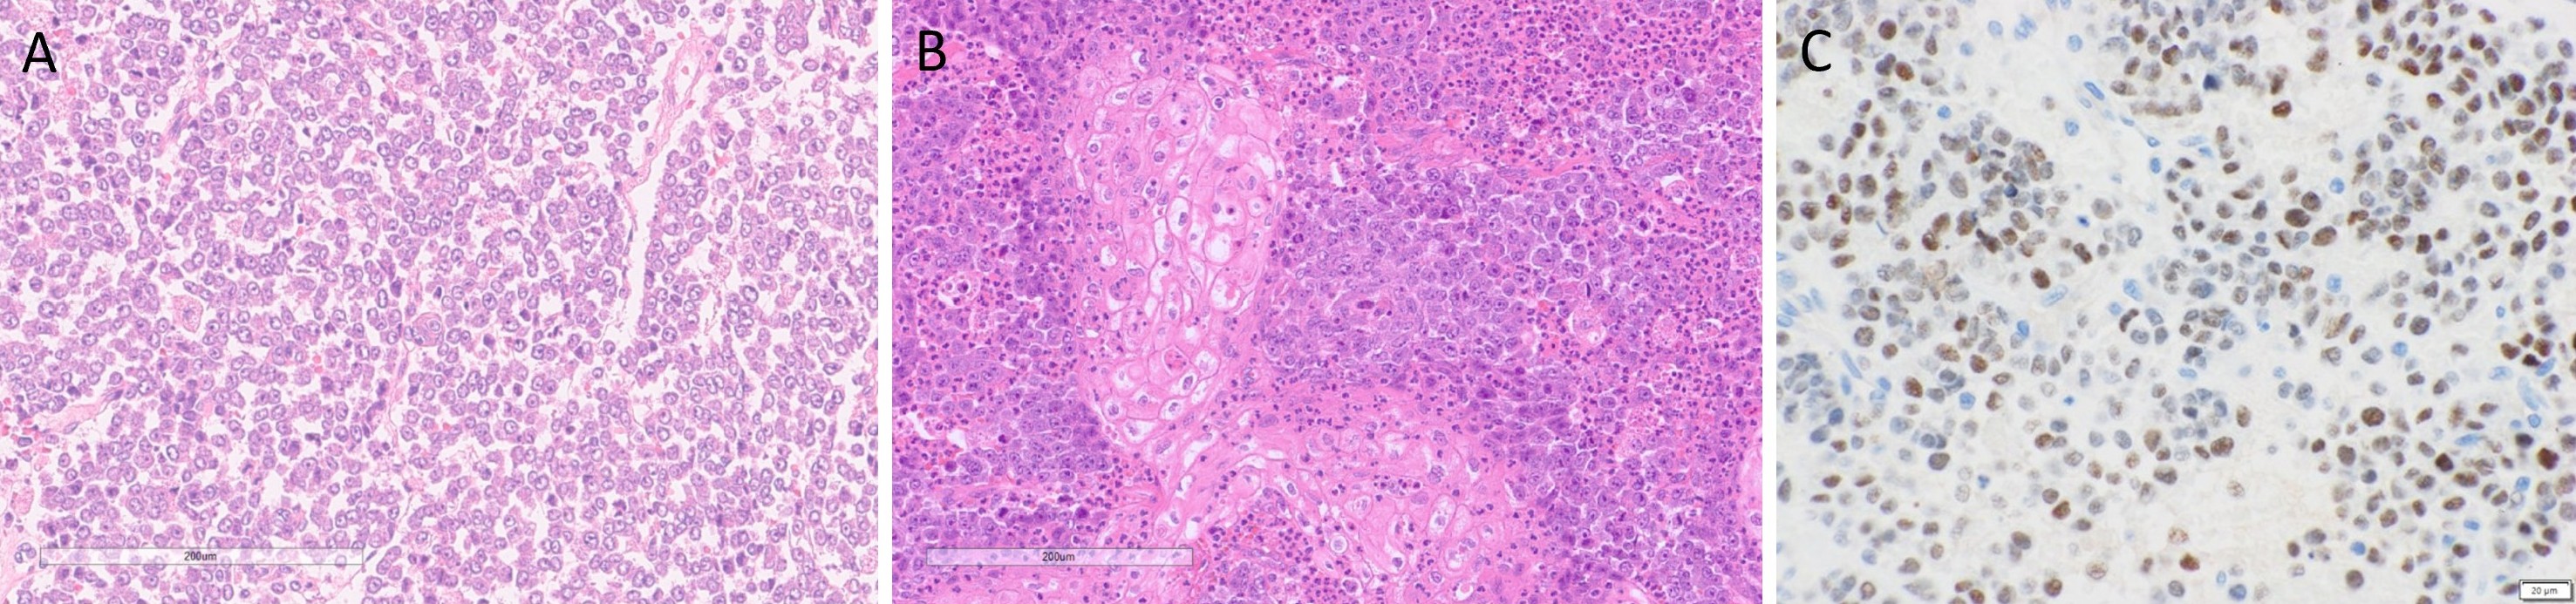

Macroscopically, the fungating tumor measured 90 × 75 × 80 mm in the superior to inferior, anterior to posterior, and superficial to deep dimensions. The cut surface was variegated, featuring firm white nodules interspersed with softer hemorrhagic regions. Histological analysis revealed an invasive carcinoma exhibiting high-grade morphological features. Tumor cells exhibited discohesion and nuclear enlargement, with an absence of overt differentiation (Figure 2A). Foci of squamous differentiation were noted, along with poorly formed glands and cribriform architectural patterns. Focal areas of keratinizing squamous differentiation were observed, accompanied by dense neutrophilic infiltration (Figure 2B). Additional findings included focal spindle cell proliferation, areas of cytoplasmic clearing, and rhabdoid morphology. Tumor cells also displayed marked nuclear pleomorphism, prominent nucleoli, and variable amounts of eosinophilic cytoplasm. Lymphovascular invasion was observed, while no perineural invasion was identified. Metastatic carcinoma was present in 42 of 47 dissected lymph nodes, with extranodal extension documented in at least four. The postoperative pathological stage was determined to be pT4aN3bM0, indicating extensive local invasion, significant regional lymph node involvement with extranodal extension, and no evidence of distant metastasis at the time of surgery.

Immunohistochemistry Results

Immunohistochemical analysis demonstrated strong cytoplasmic positivity for cytokeratin 7 and patchy expression of cytokeratin 5/6, confined to areas of squamous differentiation. P40 showed sparse nuclear staining in regions with squamous features. Extensive nuclear positivity for NUT-P4 was observed, demonstrating diffuse nuclear reactivity within tumor cells, confirming the diagnosis of NC (Figure 2C). Membranous staining for MOC31 was also noted, including within squamoid areas. P16 exhibited a patchy mosaic pattern. Expression of BRG1 and INI1 was retained, while CD56 showed rare focal positivity. Immunostains for androgen receptor protein, myogenin, synaptophysin, chromogranin, INSM1, DOG1, SOX10, smooth muscle actin, and caldesmon were negative.

Figure 2. Histopathological features of parotid NUT carcinoma. (A) Hematoxylin and eosin (H&E) staining reveals a monotonous population of tumor cells exhibiting discohesion, nuclear enlargement, and absence of overt differentiation. (B) H&E staining highlights focal areas of keratinizing squamous differentiation, accompanied by dense neutrophilic infiltration. (C) Immunohistochemical staining for NUT demonstrates diffuse nuclear reactivity within tumor cells, confirming the diagnosis of NUT carcinoma.